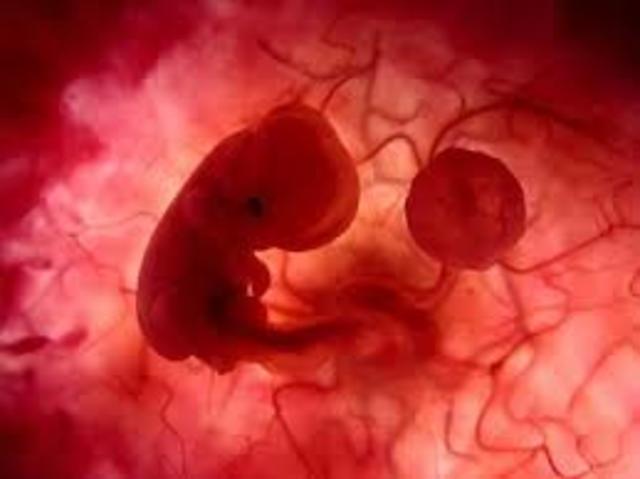

En esta semana se ha complementado la implantación del embrión humano. Su crecimiento será muy rapido a partir de este momento. El embrión aparece al centro, como un disco bilaminar y se encuentra entre dos cavidades, el amnios y el saco vitelino. Por fuera, encontramos al trofoblasto que va a formar la parte fetal de la placenta.